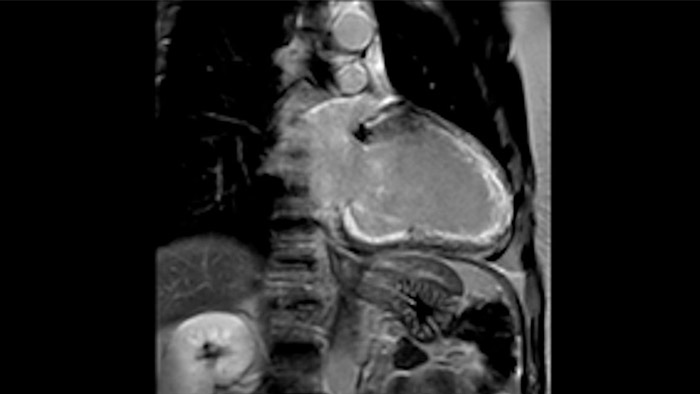

Diagnostic and prognostic utility of cardiac MR is increasing. Assess the anatomy and function of the heart using cine acquisitions, acquire information about perfusion and viability of the cardiac tissue, visualise potential edema with black blood sequence, access and even quantify tissue characterisation with CardiacQuant.